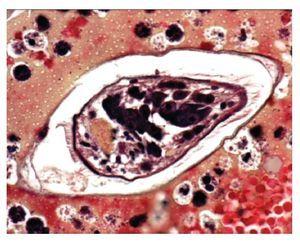

Se sospechó de esquistosomiasis por lo que se decidió darle tratamiento con prazicuantel, una sola toma (40 mg por Kg). El resultado histopatológico de la biopsia confirmó el diagnóstico de cistitis aguda y crónica hemorrágica con metaplasia epidermoide, por lesión consecutiva a S. haematobium (Imagen 6).

Imagen 6.Huevo de Schistosoma haematobium.